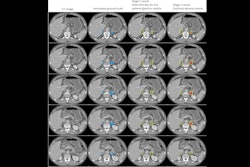

SubtleHD offers radiologists, imaging centers, and hospitals a vendor-neutral AI tool that integrates with existing MRI scanners, thus allowing facilities to run faster scans and add additional patients while enhancing diagnostic confidence, according to the firm. It denoises and sharpens images and can be used with all body parts and all contrasts, including 2D and 3D images, Subtle Medical said.